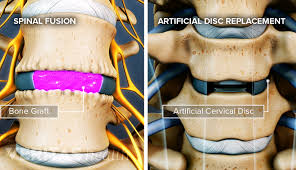

Cervical spondylosis is age related wear and tear of the neck bones and discs. It is said to affect most people by the age of 60, but commonly we even see youngsters with this problem. This results in degeneration of the disc in the neck as well as bony overgrowth.

Spine surgery can fail if there is recurrence of slip disc even after disc removal surgery. This can occur either at the same level or some other level. Sometimes, spine surgery can fail due to failure to use spine implants at the time of first surgery.